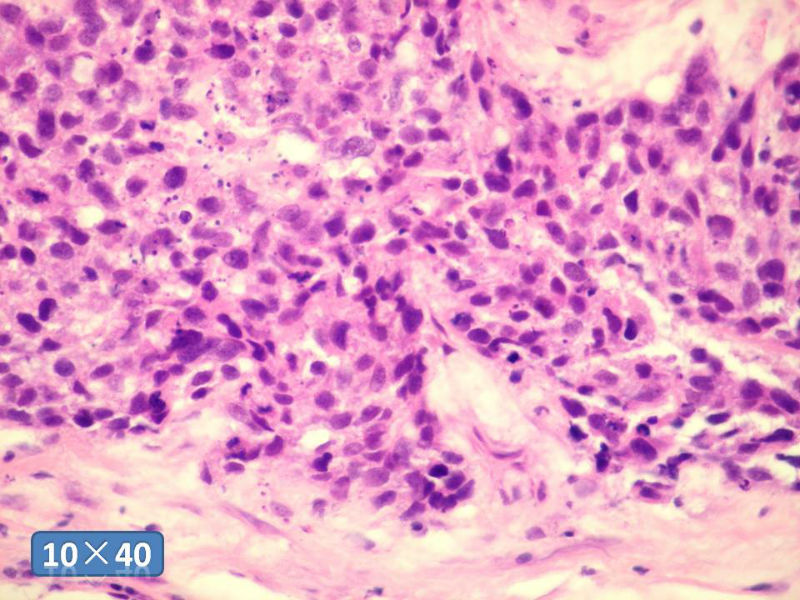

女性,50岁,乳腺肿物,冰冻切片(图1-25)

HE